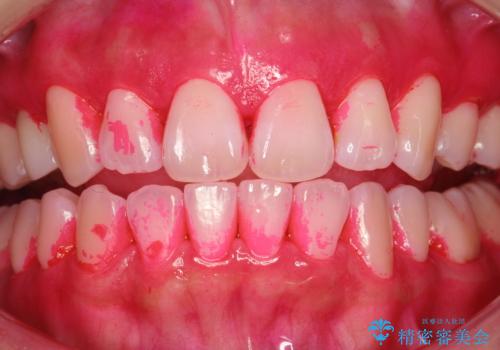

染め出しをしての歯磨き指導とPMTC

- 定期的にメンテナンスにいらしている方です。日々の歯磨きチェックもかねて染め出しとPMTC30分コースを行いました。

染め出し液を使ってプラークを染め出すことにより、普段の歯みがきで磨き残している場所を目で確かめることができます。

日々の歯磨きを上達するには、まずどこが磨けていないか認識することが大切です。